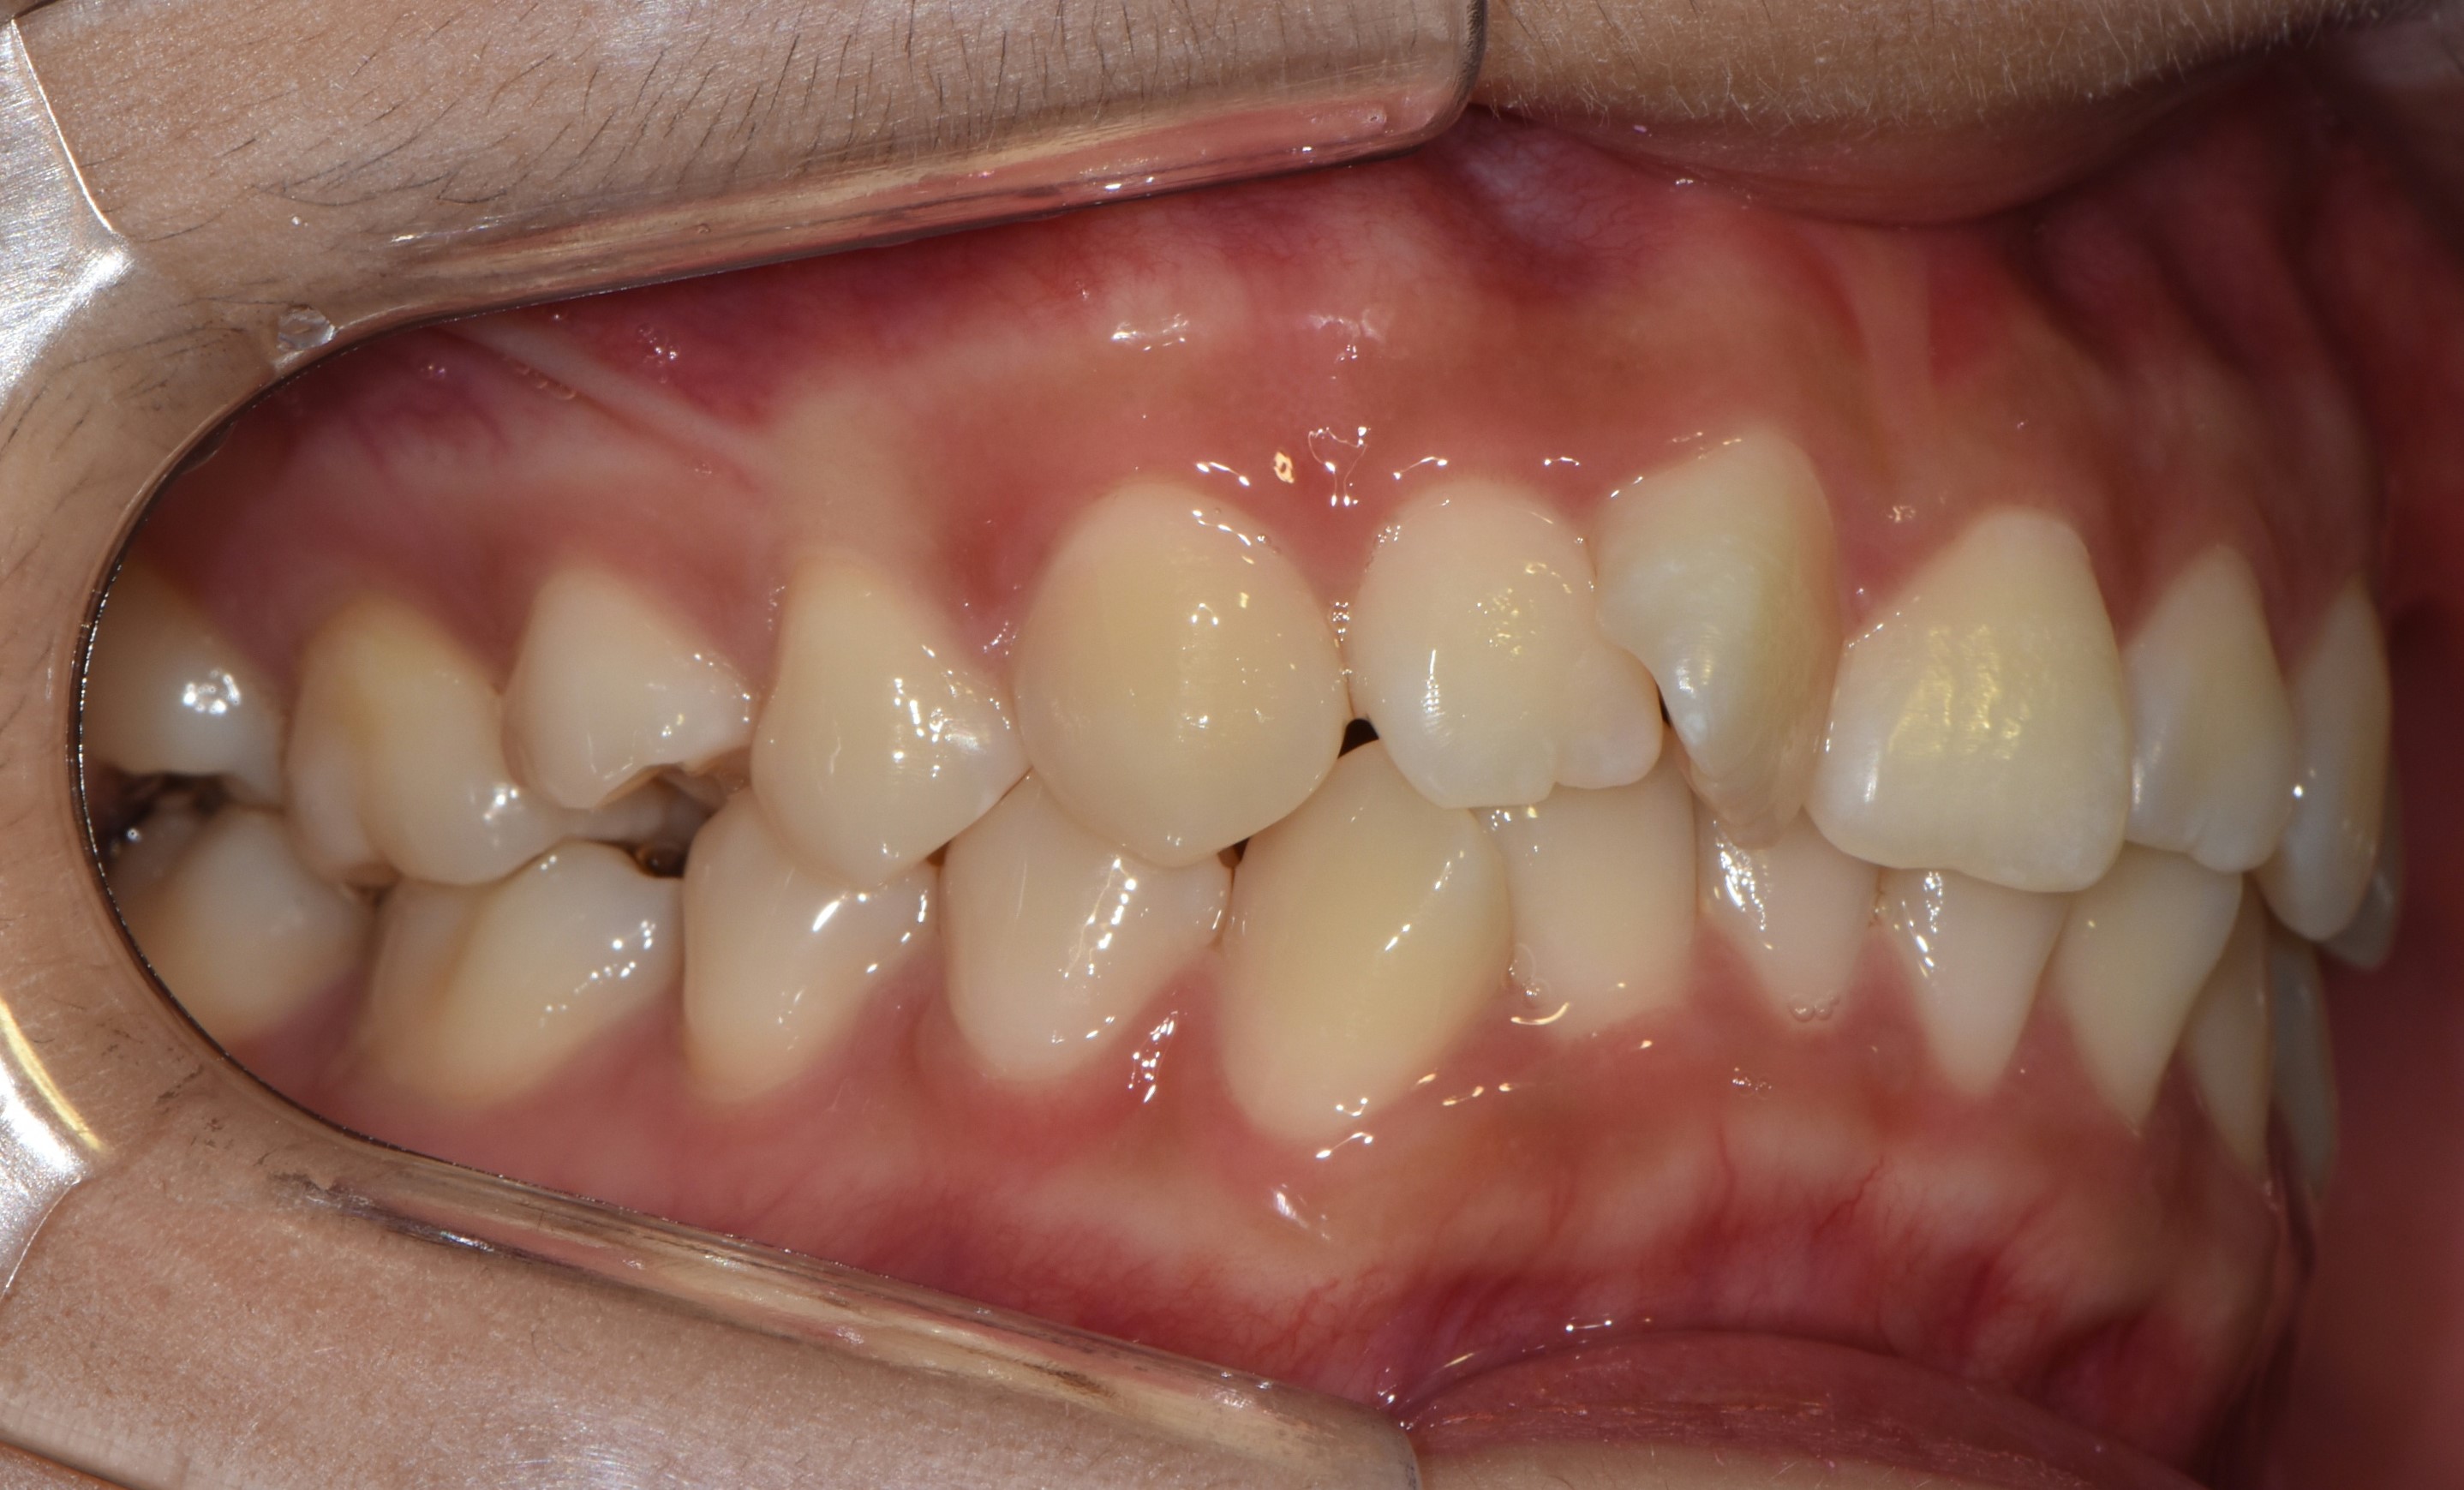

치료 전 사진입니다.